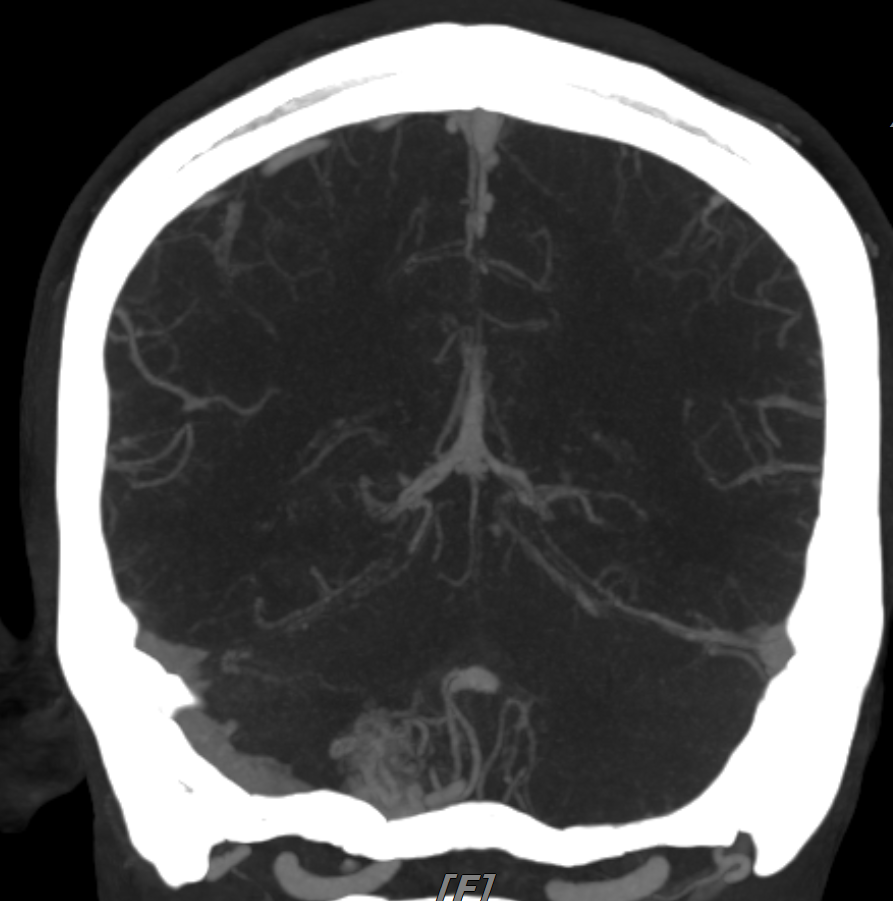

조영증강 CT나 CTA(CT angiography)을 시행하면 “뒤엉킨 벌레뭉치(bag of worms)” 같은 특징적 조영 패턴 나타난다.